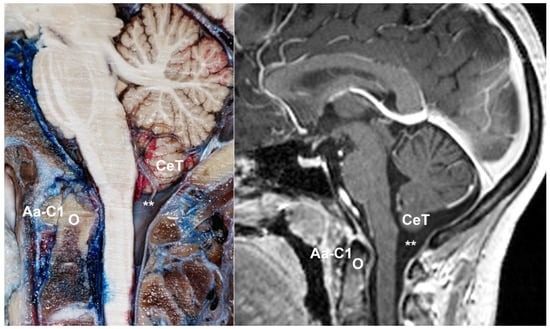

- McRae’s line (McRL). McRae’s and McGregor’s lines were described in the late 1940s to assess basilar impression in plain radiographs [102,103]. In 1953, McRae used Chamberlain’s line to evaluate different bony abnormalities in the FM region [103]; however, in a second paper, studying the occipitalization of the atlas, he defined the McRL, which has been extensively used in many studies to describe the position of the normal odontoid peg and/or cerebellar tonsils [102,103]. This line is drawn from the basion to the opisthion and represents the planum of the FM, and its length the anteroposterior width of the FM (Figure 7, line 2). In most studies and clinical practice, TH is evaluated by measuring the distance from the most caudal aspect of the tonsils to a line running perpendicular to the McRL [6,99]. However, since TH is usually asymmetrical, coronal slices are the best method to measure and evaluate it. As indicated by Raybaud and Jallo, in normal individuals, both the McRae and Chamberlain lines are superimposed but diverge when the clivus is hypoplastic [6] (Figure 8).